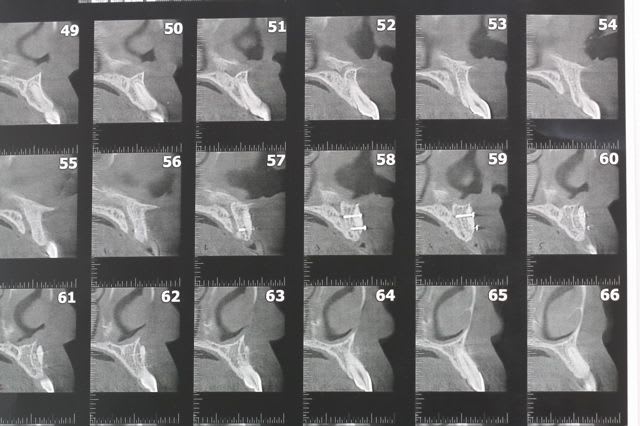

oups j'ai oublié l'OPT avant pdt et la rx après

Ramus1 f9pzlq - Eugenol

Ramus2 g3v6cg - Eugenol

R6 v9lbnf - Eugenol